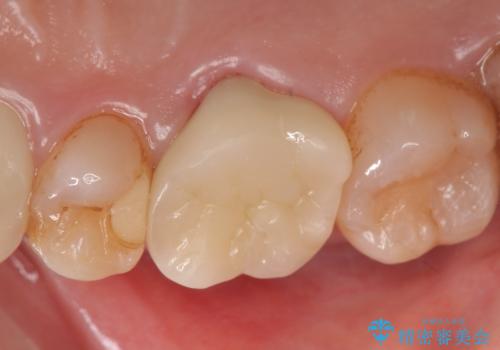

オールセラミッククラウン 他院にて治療困難と言われた歯の治療

- 右上の奥歯でものを咬むと痛むため他院を受診したが、治療は難しいと言われたため当院にいらっしゃった方の症例です。

再根管治療を行い症状の緩解を確認後、オールセラミッククラウンによる補綴を行いました。

今回用いたオールセラミッククラウンはジルコニアフレームという白い素材の上にセラミックを盛っているため、審美性が非常に高いのが特徴です。

また、ジルコニアは人工ダイヤモンドの材料にも使われているほど高い強度を持っており、そのためオールセラミッククラウンは審美性だけでなく、奥歯やブリッジの補綴も可能とするクラウンです。